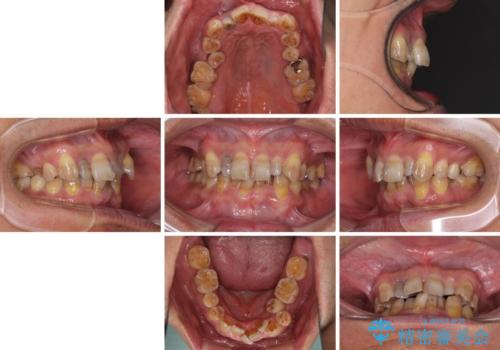

- 骨格的な咬み合わせのズレ、前歯のデコボコとクロスバイトを気にして来院された患者様です。

全額的にデコボコが強いため、上下左右の小臼歯計4歯を抜歯し、ワイヤー装置による矯正治療を行うこととしました。

抜歯する歯の一部をセオリーである第一小臼歯ではなく、第二小臼歯にすることで、骨格的なずれをカバーするように計画しました。